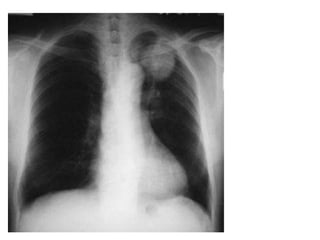

PLEURAL EFFUSION

• Pleural effusion initially manifests as basal

peripheral opacities that first fill the costo-

phrenic angle.

Curve Of Ellis

Massive Pleural Effusion